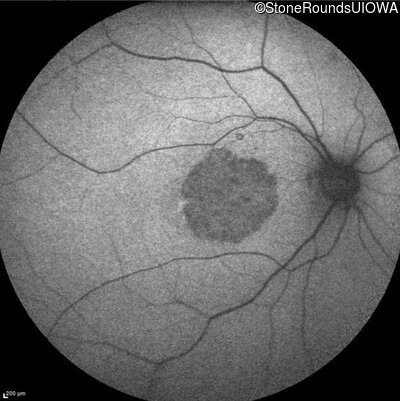

Infrared Fundus Photograph - Left - 5/400

Exemplar